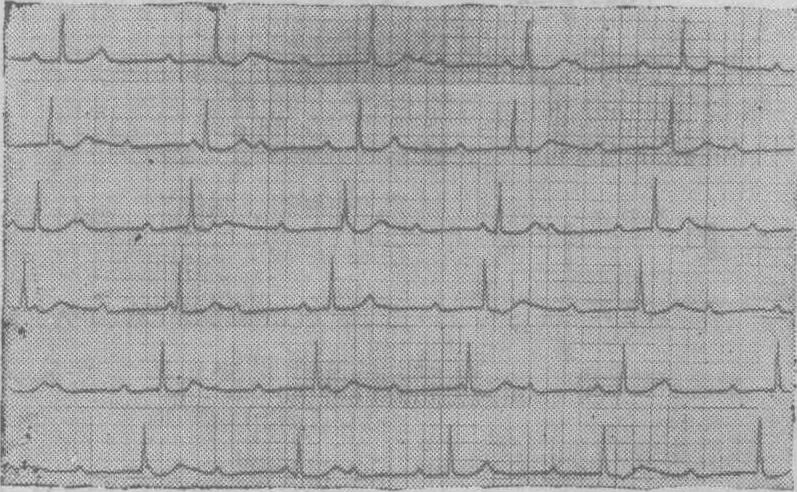

❸完全性房室传导阻滞时室上性激动全部不能下传到心室,而在单向传导时心室激动在一定的时相中能逆行传至心房,形成心房夺获(图)。

完全性房室传导阻滞伴有单向传导

Ⅱ导联连续记录: QRS波群规则缓慢,周期为1.76s,与P波无关,系房室交接处逸搏心律及完全性房室传导阻滞。除窦性P波外,另有逆行或双相P′波,P′波的发生与QRS波群有关,R-P′间期在0.24~0.20s之间,提示P′波是交接处逸搏逆传产生。当窦性与交接处逆行冲动同时激动心房时,产生双相形态的房性融合波。